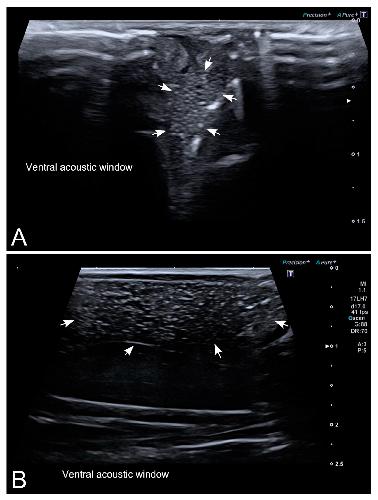

Sex Determination in Two Species of Anuran Amphibians by Magnetic Resonance Imaging and Ultrasound Techniques., Ruiz-Fernández MJ, Jiménez S, Fernández-Valle E, García-Real MI, Castejón D, Moreno N, Ardiaca M, Montesinos A, Ariza S, González-Soriano J., Animals (Basel). November 18, 2020; 10 (11):